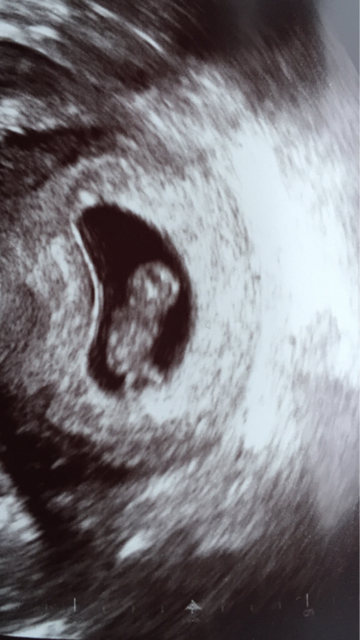

Tässä meidän juniori sillon viikko sitten rv 8+5 :)

Pienen pienet kädet ja jalan tyngät näkyvissä!